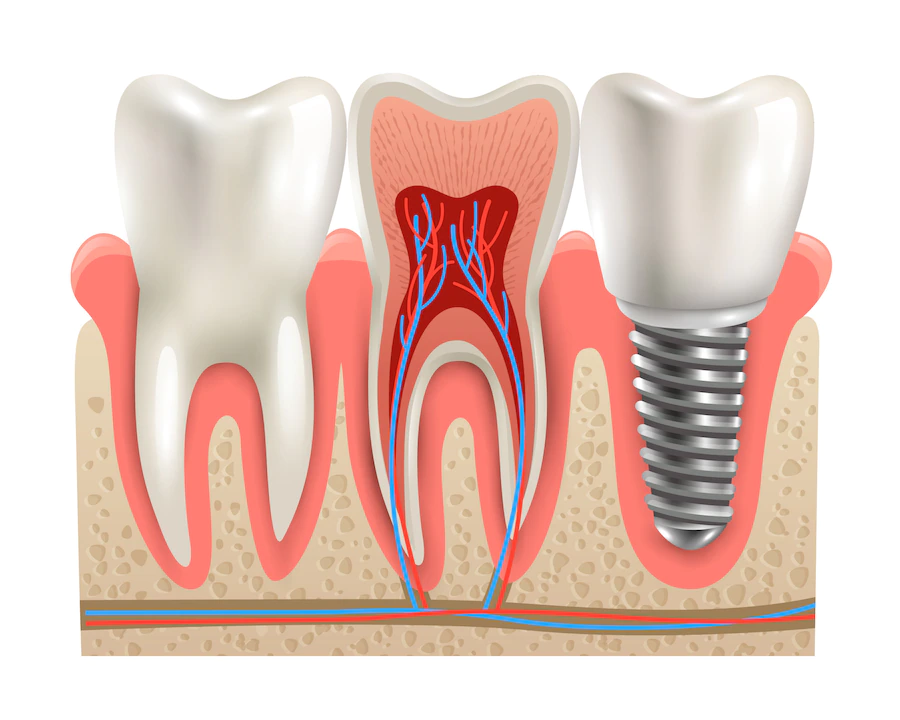

Diş İmplantı kaybedilen dişlerin yerine titanyumdan yapılmış vida benzeri yapıların çene kemiğine yerleştirilmesi işlemidir. Bu yapının üzerine yerleştirilen Protez Diş doğal dişe benzer şekilde görünür ve fonksiyonel bir çözüm sunar. İmplant Tedavisi;

Diş İmplantı kaybedilen dişlerin yerine konulabilen yapay diş kökleri olarak bilinir. Titanyum madde ile yapılan İmplantlar çene kemiğine yerleştirilir. Zaman içerisinde kemikle bütünleşip sağlam bir temel oluşturur. Bu yapı üzerine yerleştirilen Protez Diş doğal dişe benzer şekilde görünür ve fonksiyonel bir çözüm sunar.

İmplant Diş kaybedilen bir dişin yerine konulması amacıyla uygulanan Diş İmplantı Tedavisi sonucunda elde edilen yapay dişe verilen isimdir. Diş eksikliği sorununu çözmek, estetik bir gülümsemeye sahip olmak ve çiğneme fonksiyonlarını restore etmek için kullanılır.